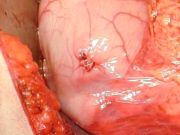

| 09:30, 7 בנובמבר 2012 | פאוכרומוציטומה714.png (קובץ) |  |

225 קילו־בייטים | Motyk | 1 | |

| 09:33, 7 בנובמבר 2012 | פאוכרומוציטומה614.png (קובץ) |  |

185 קילו־בייטים | Motyk | 1 | |

| 09:34, 7 בנובמבר 2012 | תצלוםפאוכרומוציטומה714.png (קובץ) |  |

216 קילו־בייטים | Motyk | 1 | |

| 09:36, 7 בנובמבר 2012 | פאוכרומוציטומה814.png (קובץ) |  |

195 קילו־בייטים | Motyk | 1 | |